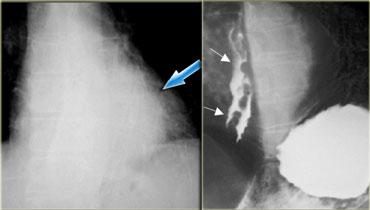

Bên trái là hình ảnh giãn tĩnh mạch thực quản hướng xuống (Downhill varices) ở bệnh nhân tắc nghẽn tĩnh mạch chủ trên do bệnh histoplasmosis.

Trên phim chụp thực quản cản quang, các khuyết đọng thuốc không hằng định (mũi tên) biểu hiện giãn tĩnh mạch hướng xuống ở thực quản trên.

Hình chụp mạch máu cho thấy các mạch máu bàng hệ bao gồm tĩnh mạch liên sườn trên trái giãn rộng (mũi tên).

Phim chụp thực quản cản quang cho thấy các khuyết đọng thuốc không hằng định (mũi tên xanh dương) do giãn tĩnh mạch hướng xuống ở thực quản trên.

CT cho thấy giãn tĩnh mạch thực quản (mũi tên đỏ) và trung thất.

Tiếp tục xem hình chụp tĩnh mạch.

Hình chụp tĩnh mạch chi trên cho thấy tắc nghẽn tĩnh mạch chủ trên (SVC).